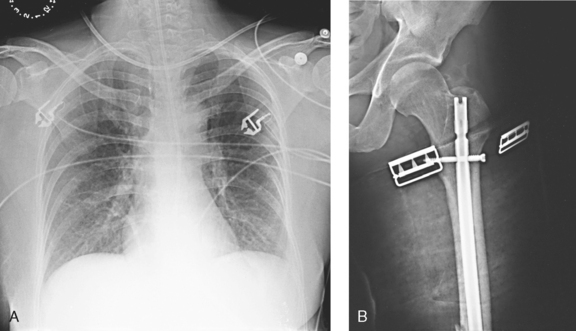

Fig. 28-3 Mobile radiograph of proximal femur and hip, showing comminuted fracture of left acetabulum. A, Poor-quality radiograph resulted when grid was transversely tilted far enough to produce significant grid cutoff. B, Excellent-quality repeat radiograph on the same patient, performed with grid accurately positioned perpendicular to central ray.

Fig. 28-11 Mobile AP chest radiographs in critically ill patients. A, Patient with postoperative left thoracotomy and chest tube, infiltrate or atelectasis in the left base, segmental elevation of the right hemidiaphragm, and soft tissue emphysema on the left. B, Patient with small left pleural effusion and moderate right effusion, cardiomegaly, mild pulmonary vascular congestion, and calcification and torsion of the aorta.